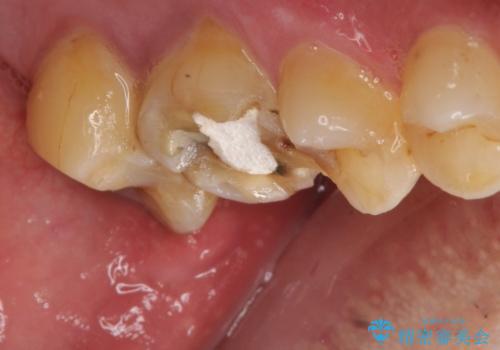

- 治療計画

根管治療を行ったのち、症状改善を認めオールセラミッククラウンにて修復治療を行いました。

根管治療にはラバーダムシートをつけて行うことが大切です。マイクロスコープを使用し治療を行いました。治療後、歯の痛みは消失し、とても満足していただきました。

根管治療を行った歯は、再発防止や残された歯質を守るため、クラウンによる補綴治療が必要となります。